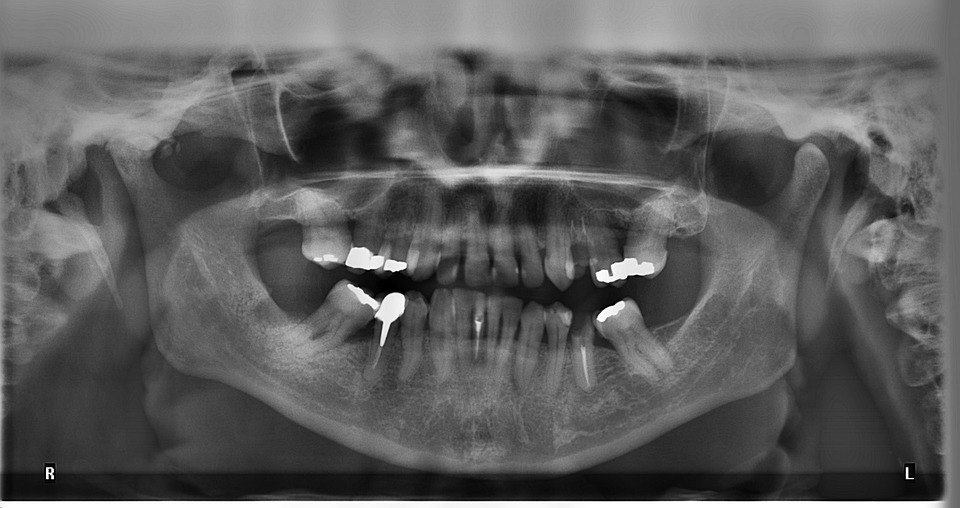

- The dentist examines the tooth, often using X-rays to assess the extent of decay. Local anesthesia may be administered to minimize discomfort.